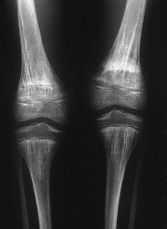

Para descartar una enfermedadsistematizada (por ejemplo, metástasis osteocondensantes) serealiza un estudio radiológico esquelético donde seencuentran imágenes similares de moteado irregular a nivelde muñecas y manos (fig. 2), pies (fig. 3), y rodillas (fig.4).

Figura4.

El cuadro corresponde a unaosteopoiquilia puntiforme descartándose otro tipo depresentación mucho más rara, la osteopoiquiliaestriada, caracterizada por imágenes condensantes en formade estrías verticales (fig. 5).